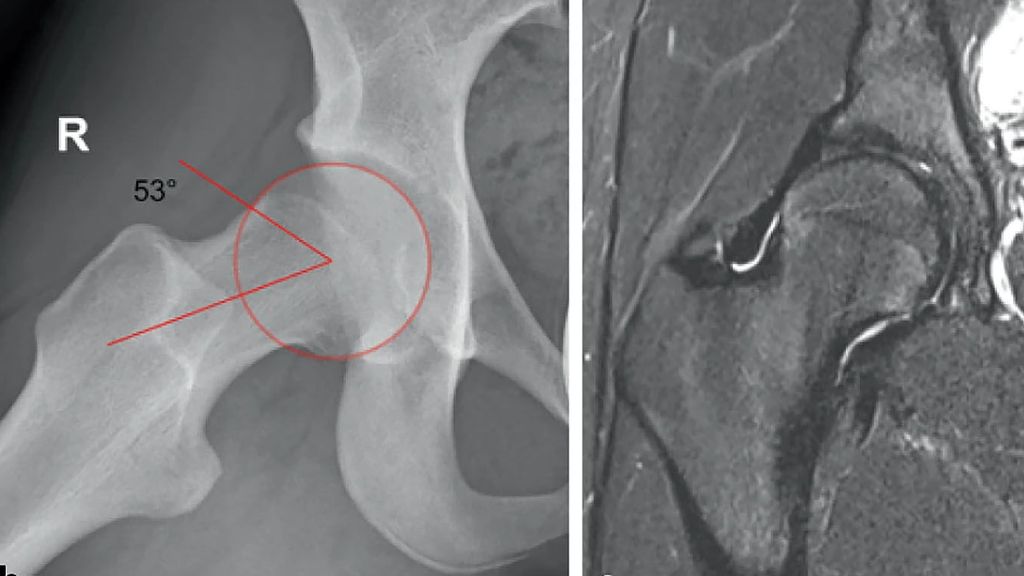

Abb. 1: 14-jährige aktive Balletttänzerin mit Schmerzen bei starker Abduktion und Außenrotation. Im Projektionsröntgen ap (a) zeigt sich eine Grenzdysplasie (LCE-Winkel 18°, Tragflächenwinkel 14°), in der Dunn-View (b) ein verminderter femoraler Offset mit einem Alpha-Winkel von 53,4°. Die MRT (c) zeigt ein geringgradiges Knochenmarködem am Kopf-Schenkelhals-Übergang als Zeichen des FAI (aus Chiari et al. 2022)5